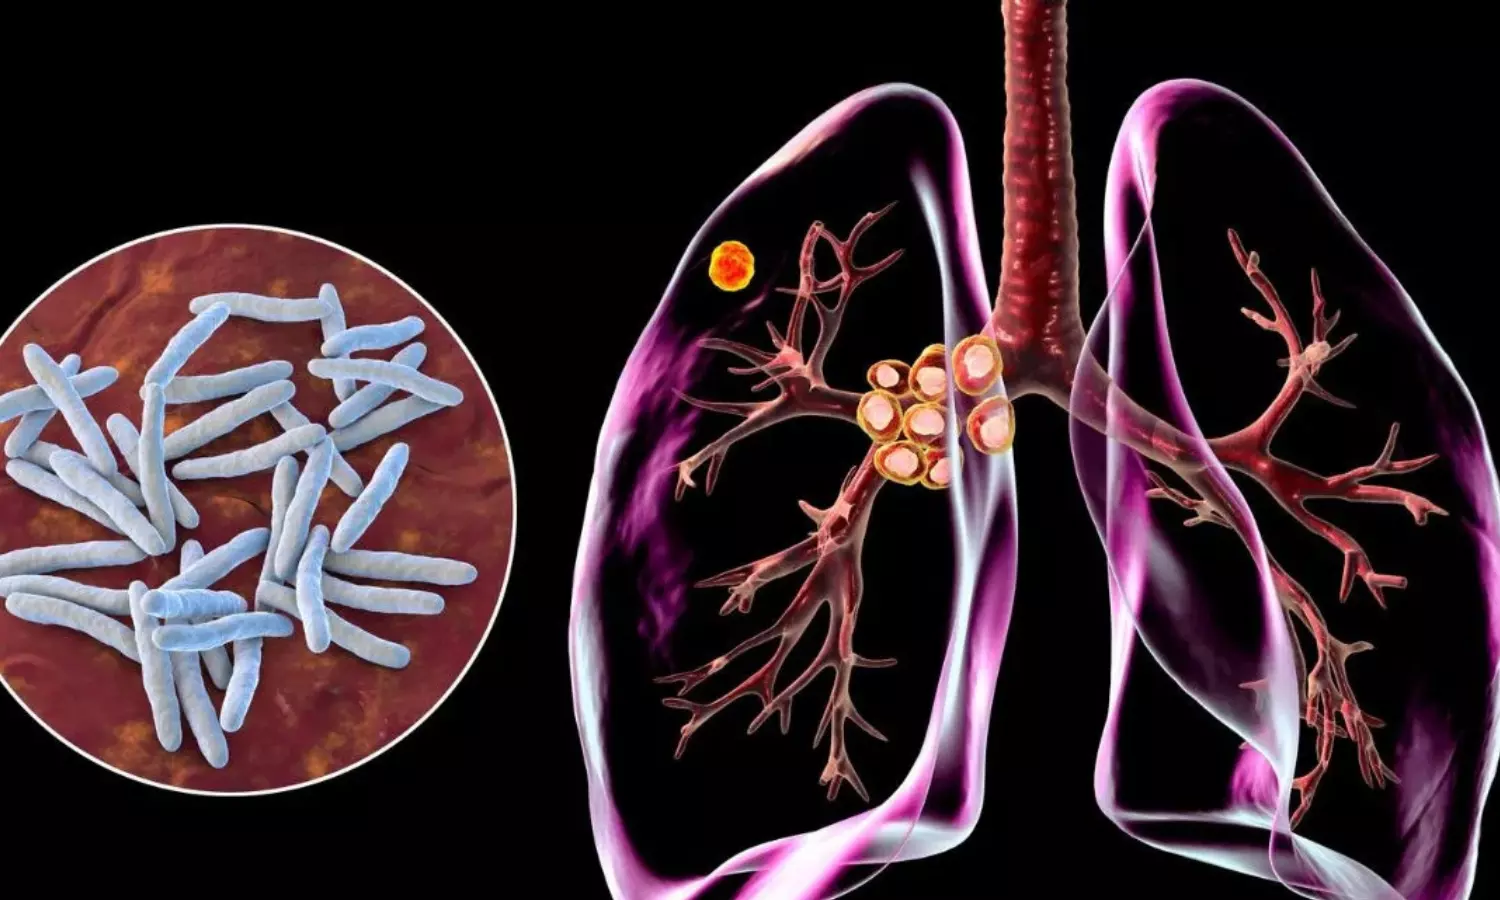

Tuberculosis symptoms:ప్రతి ఏటా మార్చి 24న ప్రపంచవ్యాప్తంగా 'ప్రపంచ క్షయవ్యాధి (TB) నివారణ దినోత్సవం' నిర్వహిస్తారు. ప్రాణాంతకమైన ఈ అంటువ్యాధిపై ప్రజల్లో అవగాహన పెంచడమే ఈ రోజు ప్రధాన ఉద్దేశ్యం. నేటికీ భారతదేశంతో సహా ప్రపంచవ్యాప్తంగా టీబీ కేసులు ఆందోళనకరంగా నమోదవుతున్నాయి. అయితే, టీబీ లక్షణాలపై సరైన అవగాహన లేకపోవడమే ఈ వ్యాధి విజృంభించడానికి ప్రధాన కారణమని వైద్య నిపుణులు హెచ్చరిస్తున్నారు.

ఈ వ్యాధి లక్షణాలపై పలువురు వైద్య నిపుణులు కీలక విషయాలను వెల్లడించారు. సాధారణ దగ్గుకు, టీబీకి మధ్య ఉన్న తేడాను గుర్తించడం చాలా ముఖ్యం అని సూచించారు. మీకు దగ్గు ప్రారంభమై రెండు వారాలు దాటినా తగ్గకపోతే, దానిని సాధారణ దగ్గుగా భావించకూడదని, వెంటనే వైద్యుడిని సంప్రదించాలని చెప్పారు. దగ్గినప్పుడు కఫం పడటం, మరీ ముఖ్యంగా కఫంతో పాటు రక్తం పడటం టీబీకి ప్రధాన సంకేతం అని వెల్లడించారు. ఎలాంటి కారణం లేకుండా వేగంగా బరువు తగ్గడం, ఆకలి మందగించడం కూడా టీబీకి లక్షణాలు అని చెప్పారు. శ్వాస తీసుకున్నప్పుడు లేదా దగ్గినప్పుడు ఛాతీలో నొప్పి రావడాన్ని నిర్లక్ష్యం చేయకూడదని అన్నారు.

టీబీ వ్యాధి ప్రారంభ దశలో చాలా నెమ్మదిగా ప్రభావం చూపుతుందని, దీనివల్ల అనేక మంది రోగులు తాము బాగున్నాము కదా అని భ్రమపడతారని డాక్టర్లు వివరించారు. అవగాహన లేకపోవడం వల్ల చాలా మంది వైద్యుడి దగ్గరకు వెళ్లడంలో ఆలస్యం చేస్తారని, దీనివల్ల ఆ వ్యాధి ముదిరి ఊపిరితిత్తులు దెబ్బతినే ప్రమాదం ఉందని చెప్పారు. ఒకవేళ మీకు పైన పేర్కొన్న లక్షణాలు కనిపిస్తే వెంటనే పల్మనాలజిస్ట్ను సంప్రదించాలని నిపుణులు సూచించారు. వారు ప్రధానంగా ఈ పరీక్షల ద్వారా వ్యాధిని నిర్ధారిస్తారని వెల్లడించారు. ఛాతీ ఎక్స్-రే, కఫం పరీక్ష, రక్త పరీక్షలు..